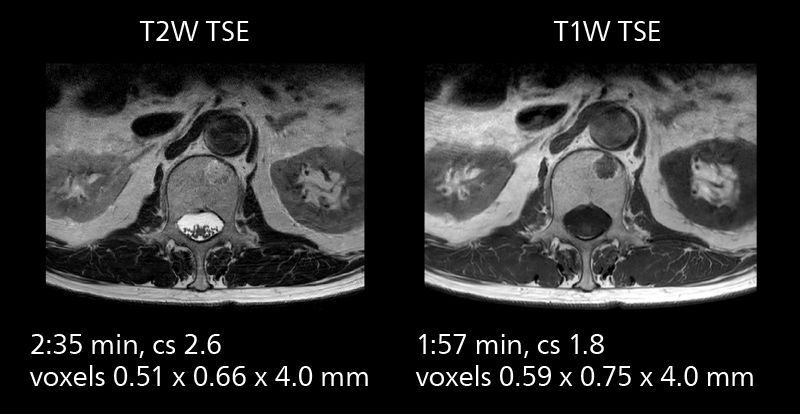

The high performance of the Vega HP gradients is particularly impressive in DWI. “The Vega HP gradients enable us to scan faster and use b-values as high as 2000, for example in prostate DWI and in DWIBS, which provides image quality that is remarkably improved over the previous system and we are able to more easily see lesions.”

Examples of prostate imaging showing faster scan times and improved resolution illustrate the power of SmartPath to Elition X in this case of prostate cancer with PI-RADS score 4.